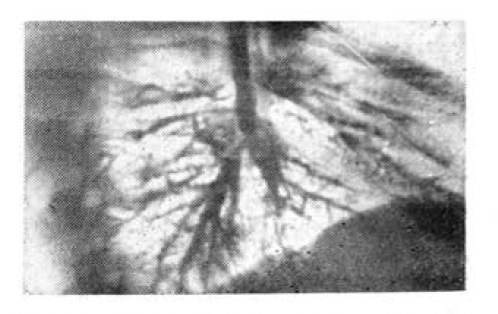

С целью выявления ателектатических бронхоэктазов произведена попытка селективной бронхографии средней и нижней долей. Бронхи не контрастируются (рис. 2), а контрастная масса забрасывается в левое бронхиальное дерево. Осуществлена аспирация контрастной массы с последующим введением антибиотиков.

Рис. 2. Бронхограмма через 15 дней после извлечения пружины. В нижнедолевом бронхе контрастная масса отсутствует.